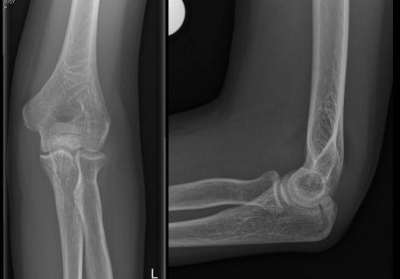

2 / 10

2. Observe esta imagem. Que estrutura corresponde ao número 5?

3 / 10

6. Em relação aos cortes acima, da esquerda para direita, qual alternativa está correta?